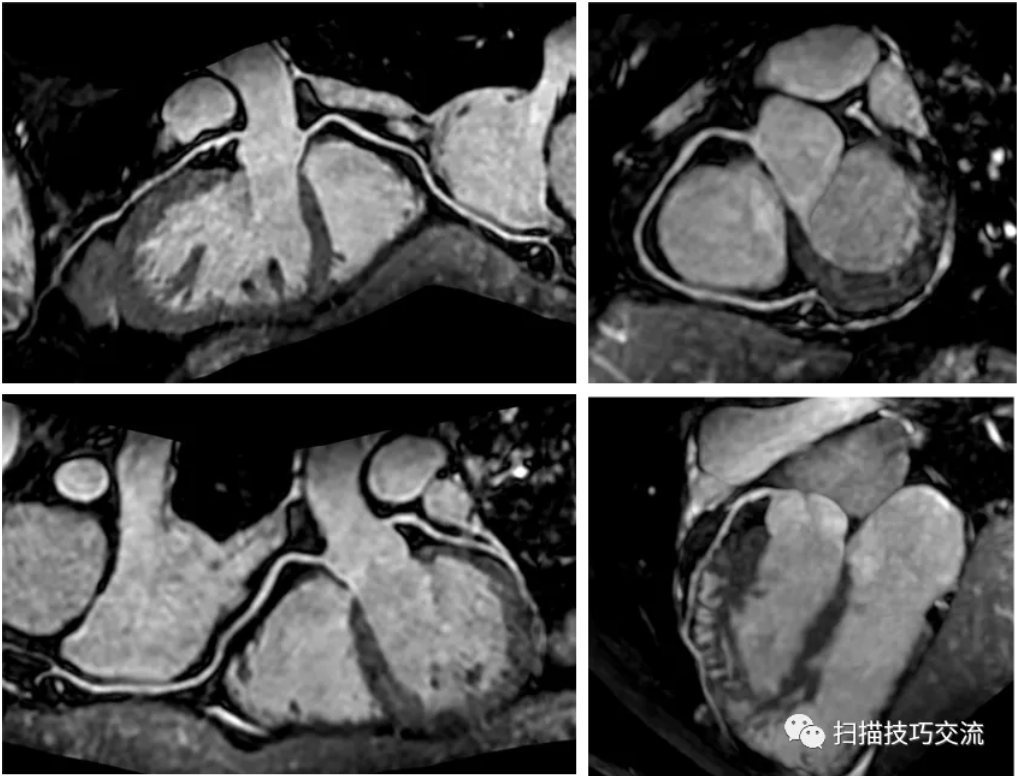

3,成像效果

图像来自浙江大学第一附属医院,非常感谢汪启东教授商德胜教授提供图像。